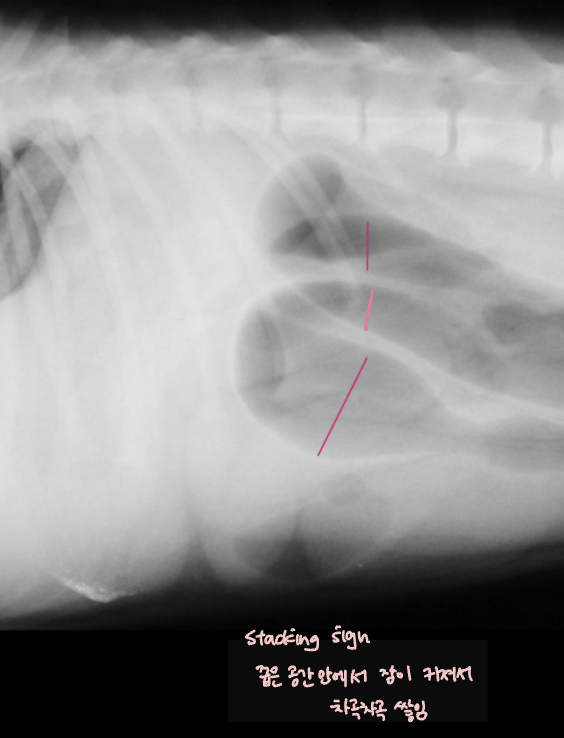

| Stacking sign |

| ์ฅ์ด ์ปค์ ธ์ ์ข์ ๊ณต๊ฐ ์์ ์ฐจ๊ณก์ฐจ๊ณก ์์ด๋ฉฐ ๋ณด์ด๋ sign. |

![]() |